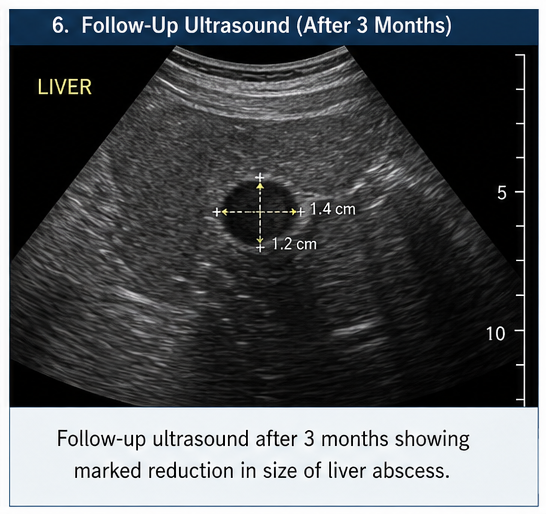

At 3 Months

The patient resumed normal activities with good compliance to therapy.